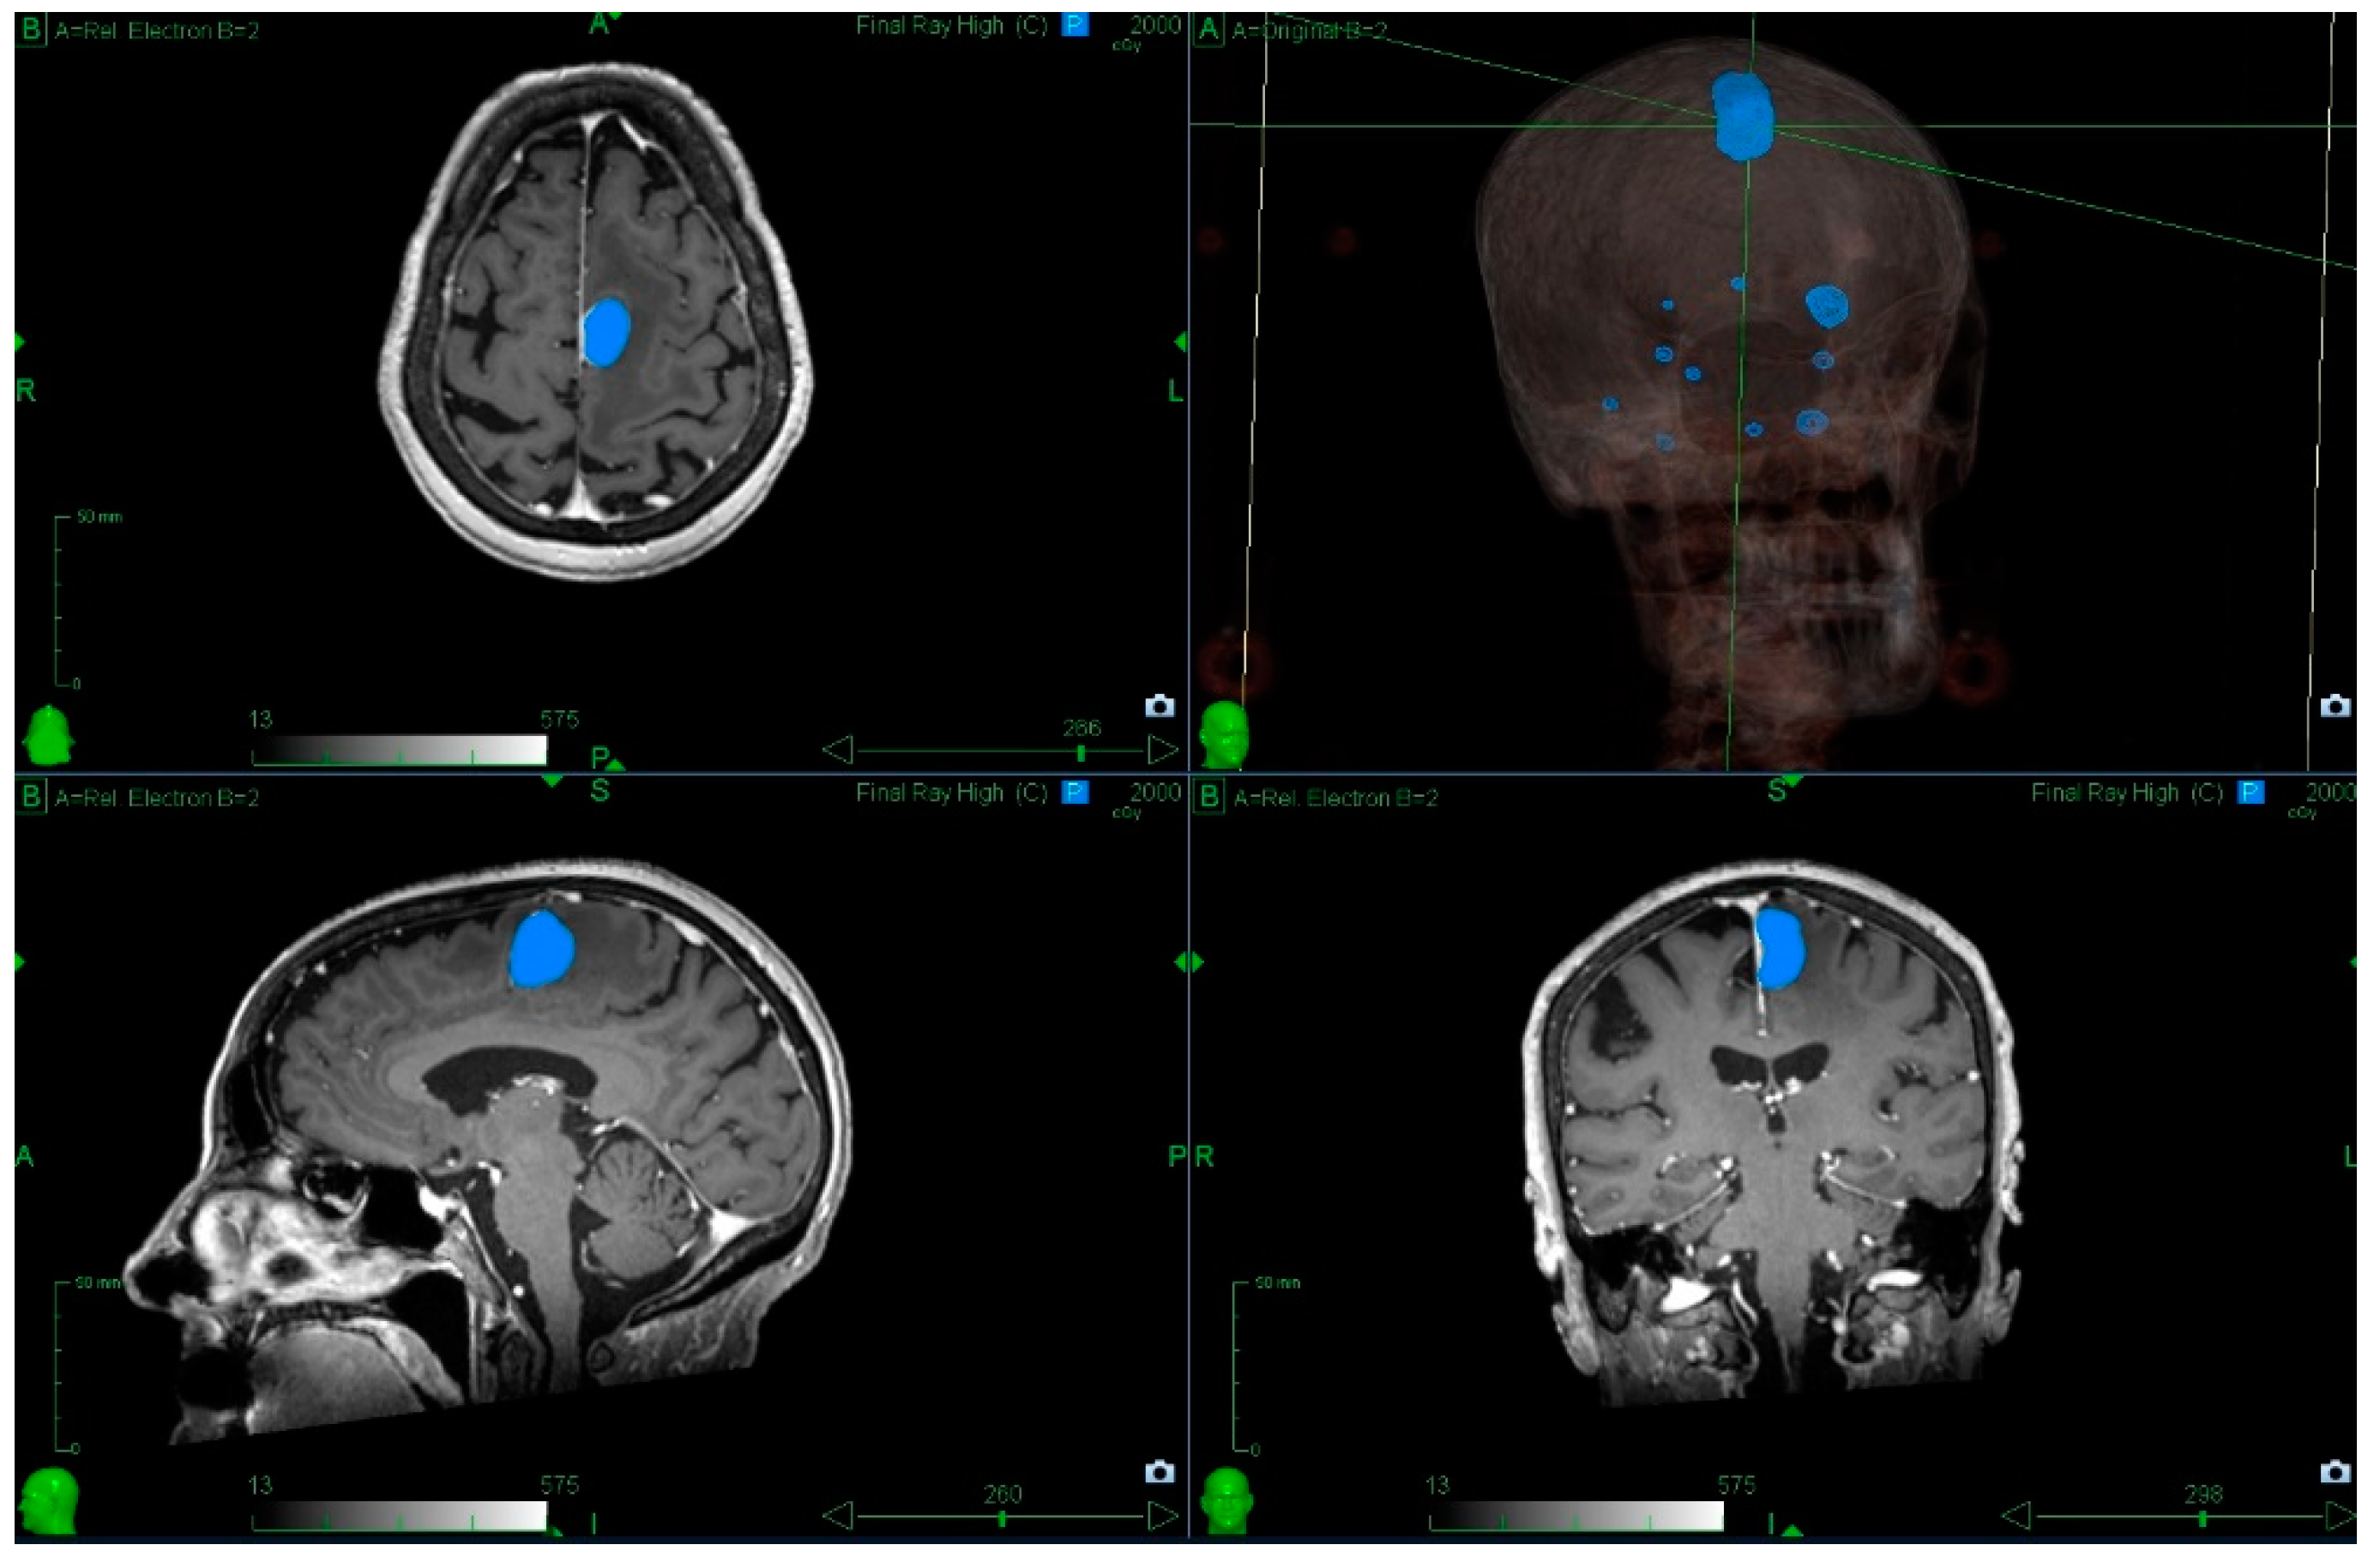

3.3. The Role of Radiosurgery for Multiple Metastases